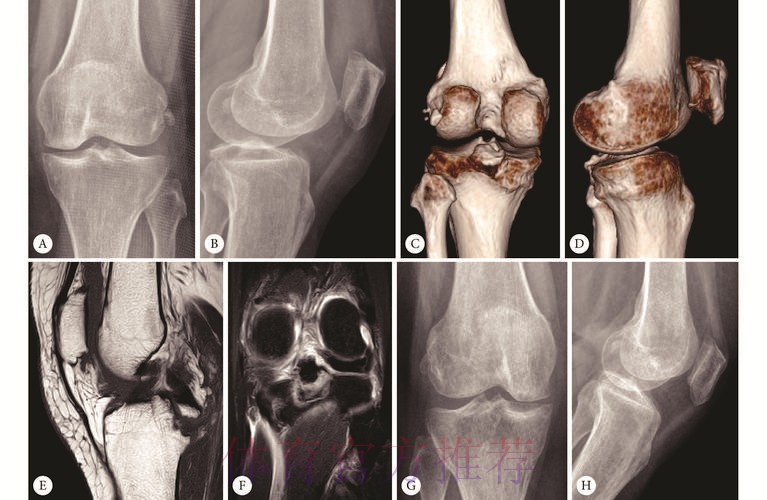

在医学角度上,膝关节稳定性主要依赖前交叉韧带、后交叉韧带以及内外侧副韧带,其中后交叉韧带负责制约小腿向后移位,并参与膝关节在屈伸、旋转中的稳定控制。对于职业球员而言,一旦出现左膝后交叉韧带扭伤,即便不是完全断裂,也意味着关节在最大爆发下的可靠性下降。高速启动、急停、防守端对抗中的身体对撞,都可能成为再次受伤的诱因。皇马医疗团队在制定康复计划时必须在“尽快复出”和“长期职业寿命”之间找到一个微妙平衡点,这种平衡往往比球迷想象的更加残酷。